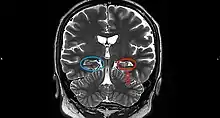

Hippocampal sclerosis (HS) or mesial temporal sclerosis (MTS) is a neuropathological condition with severe neuronal cell loss and gliosis in the hippocampus.[1] Neuroimaging tests such as magnetic resonance imaging (MRI) and positron emission tomography (PET) may identify individuals with hippocampal sclerosis.[2] Hippocampal sclerosis occurs in 3 distinct settings: mesial temporal lobe epilepsy, adult neurodegenerative disease and acute brain injury.[2][3]: 1503

On a MRI T2-weighted or T2–fluid‐attenuated inversion recovery (FLAIR) scan, hippocampal sclerosis appears as an increased signal, smaller sized (atrophic) hippocampus with a less well-defined internal structure.[2] Increased signal means that hippocampal sclerosis will appear brighter on the MRI image. Less well-defined internal structure means the expected sharp boundaries between hippocampal gray and white matter structures are absent.[2] The total volume of the hippocampus is also reduced.[2] The reduced volume arises from neuronal cell loss, and increased signal arises from gliosis.[2]